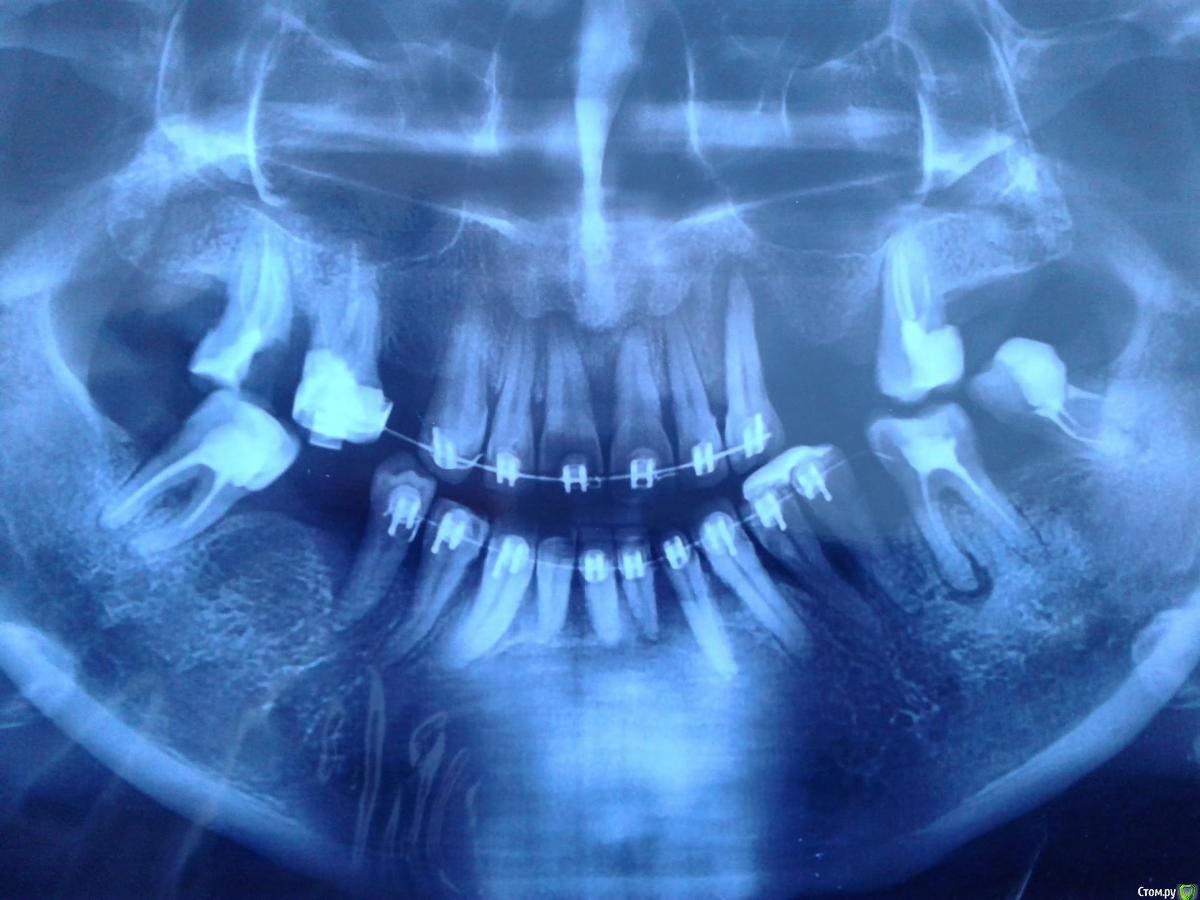

Нюра_А Опубликовано 25 октября, 2016 Поделиться Опубликовано 25 октября, 2016 Доброго времени суток!Я сразу извиняюсь, что спрашиваю на форуме, понимаю, что надо к стоматологу, пойду только на выходных. Но такой вопрос. По некоторым причинам не занималась своими зубами, точнее лечила у стоматолога(вырывала, пломбировала, удаляла зубной налет), но примерно 2 года не появлялась. Сказал, что десна совсем слабые, не лечила их.(знаю, что зря и что моя вина). Решила выровнить зубы, поставить брекеты, врач сказал, что только мосты, брекетами он не занимается, но зубы хорошие. В другой клинике(неплохой по отзывам) мне согласились поставить брекеты, но вначале хотели удалить зуб та нижней челюсти впереди. Я попросила сохранить его, решили попробовать. Брекеты ношу 9 месяцев, примерно два месяца назад появилось припухлость на зубе, потом "это" лопнуло, оголилась костная ткань. Стоматолог, что ставил брекеты, сказал, что вероятно был стоматит, который спровоцировал это, прописал мазь заживляющую, меня это насторожило. И вновь настаивал на удалении зуба(другого). Консультировалась у другого врача, он сразу мне сказал, что брекеты вообще нельзя было ставить, фундамент слабы(его слова), нужно что все зубы удалять и ставить имплантанты. А подвижность зубов-это слабые десна, я-то радовалась вместе с врачем в клинике, что зубы поддаются лечению и активно выравниваются. Тихо сижу в шоке, сама виновата, что не лечила десна.Теперь такой вопрос, как вы думаете, срочно снимать брекеты, удалять этот зуб с оголившейся десной(дыркой) и ставить туда имплантант или можно сохранить зуб? Боюсь даже опять идти в ту клинику. Готова снять брекеты, пусть это было зря, пусть кривые зубы, но свои. Снимок до брекетов прилагаю, второй врач даже не глядя на меня сказал, что брекеты-это было потеря времени и денег Ссылка на комментарий

Нюра_А Опубликовано 26 октября, 2016 Автор Поделиться Опубликовано 26 октября, 2016 (изменено) Спасибо за отзыв на сообщение! Сделала на обеде снимок Изменено 26 октября, 2016 пользователем Нюра_А Ссылка на комментарий